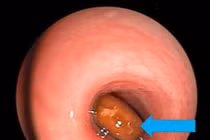

Bệnh nhi 3 tuổi gặp nguy hiểm do dị vật kim chọc tủy trong khí quản, các bác sĩ đã nội soi lấy ra thành công.